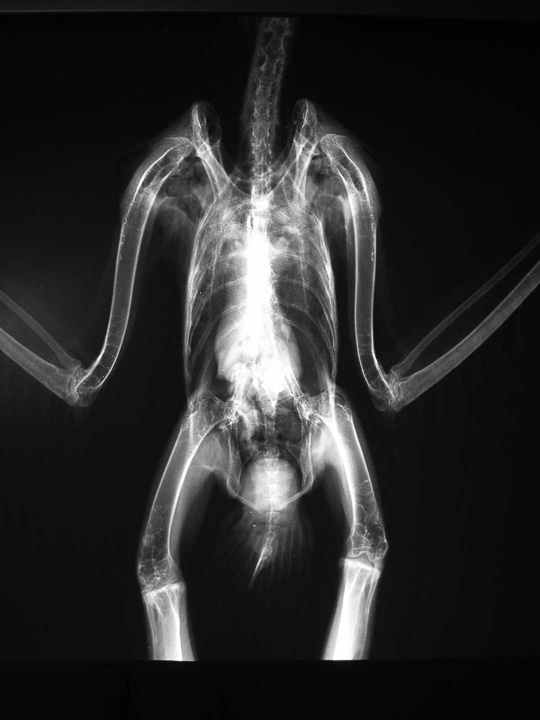

Bird XRays Long Beach Animal Hospital

From lbah.com

Bird XRays Long Beach Animal Hospital Kiwi Bird X Ray Egg According to the audubon society, a kiwi egg can can. Unlike flying birds, kiwis have relaxed constraints on their weight, and this is reflected in aspects of their anatomy such as their more solid bones. From most extreme animals on animal planet, footage of a kiwi laying an egg, complete. Genus apteryx) are famous for laying an enormous egg in. Kiwi Bird X Ray Egg.

Bird XRays Long Beach Animal Hospital Kiwi Bird X Ray Egg From most extreme animals on animal planet, footage of a kiwi laying an egg, complete. According to the audubon society, a kiwi egg can can. Unlike flying birds, kiwis have relaxed constraints on their weight, and this is reflected in aspects of their anatomy such as their more solid bones. Most strikingly, without needing to. By comparison, the kiwi egg. Kiwi Bird X Ray Egg.